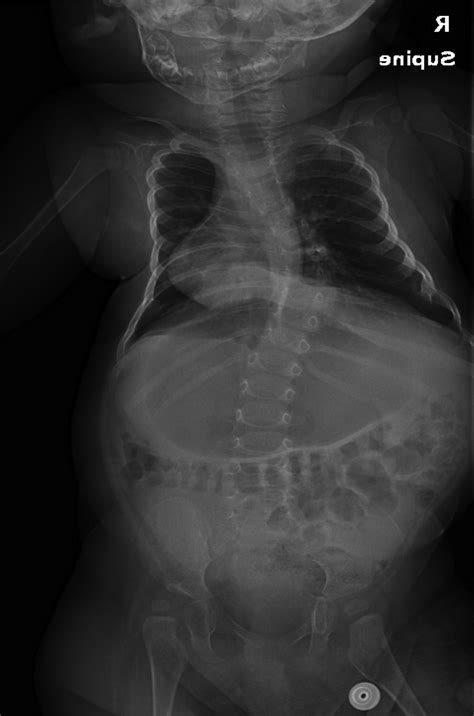

Magnetic Growth Rods Will Soon Improve Life With Early Onset Scoliosis

Facing Early Onset Scoliosis | National Scoliosis Center